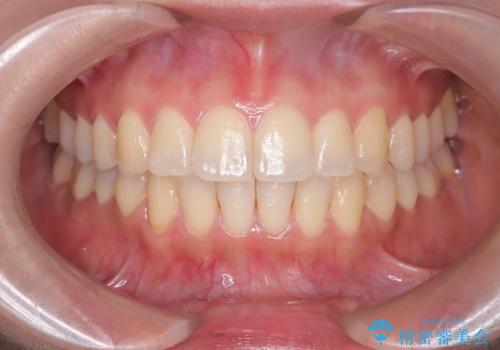

短期間での治療終了を希望され、ワイヤー矯正にて治療を行い1年ほどで治療を終了しております。

下顎前歯は矯正後補綴治療を行なっております。

期間や仕上がりで大変満足していただきました。